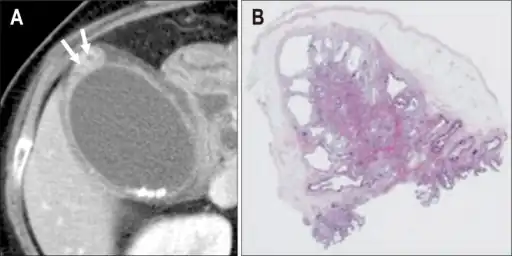

Individual with adenomyomatosis a) Axial computed tomography image b) photomicrograph- Adenomyomatosis of the gallbladder as seen on ultrasound[7]

Magnetic resonance imaging also plays an important role in the diagnosis of Rokitansky–Aschoff sinuses.[10] In fat-suppression MRI, RAS present with small, rounded, high signal intensity foci, called “pearl necklace sign”.[9]